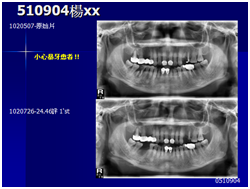

患者的原始片 91/06/13

患者陳先生於91/06/03初診,為一個牙周病患者,合併有右下缺牙。經過保守性牙周處理後,於91/08/14放置右下三顆植體。

完成後大約半年至一年進行一次例行性追蹤檢查,並無特別問題。以下為96/08/13時的追蹤小片,可以見到當時三顆植體的骨高度並無顯著變化。但右下第一小臼齒此時發現有搖動度增加的情形,當時對該顆牙做了咬合調整,降低咬合功能負荷,希望能有所改善。

96/08/13